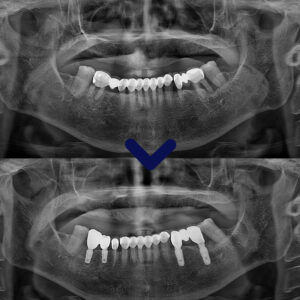

치료 전, 후 사진을 보시게 되면

염증이 깔끔하게 제거되고 남가좌동임플란트가

안정적으로 식립되어 잇는 모습과

시린 증상이 있던 치아의 뿌리 끝까지

신경치료가 마무리되어 있는 모습을 보실 수 있습니다.